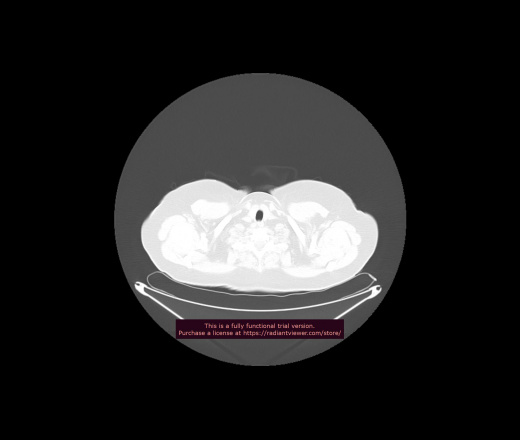

Уважаемые коллеги, если имеется интерес, сможете ли Вы спрогнозировать дальнейшее +-одинаковое течение процесса у 4 данных разных пациентов? Зацепиться где-то можно очень просто, где-то нельзя.